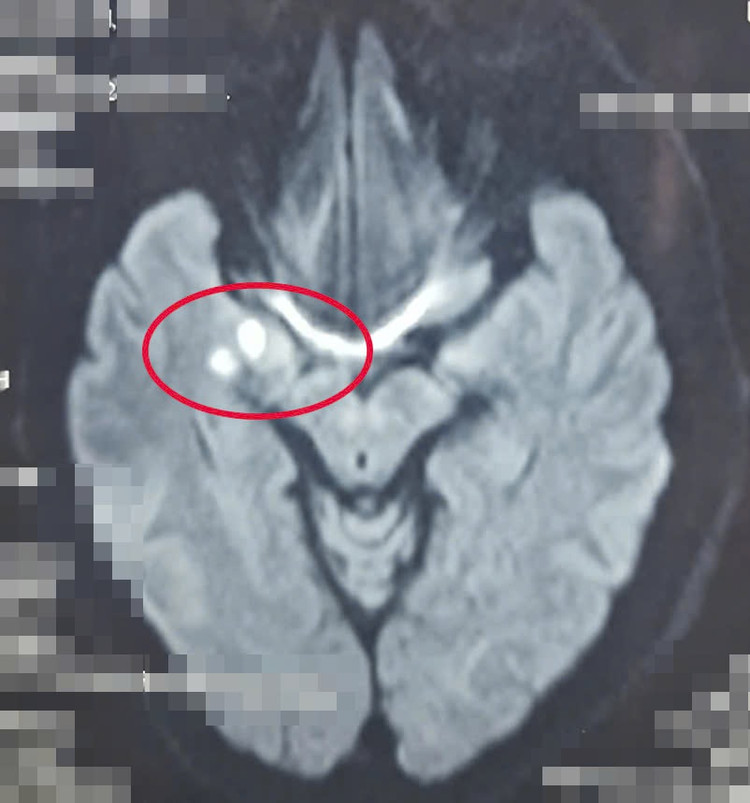

| Bệnh nhân có cục máu đông gây tắc nghẽn mạch máu, dẫn đến đột quỵ Ảnh: BVCC |

Ngay khi tiếp nhận tại khoa cấp cứu các bác sĩ tiến hành các bước thăm khám, thực hiện cận lâm sàng, chú N. được chẩn đoán đột quỵ nhồi máu não giờ thứ 2, còn trong “giờ vàng” nên được bác sĩ chỉ định sử dụng thuốc tiêu sợi huyết (rTPA) giúp tan cục máu đông gây tắc nghẽn mạch máu dẫn đến đột quỵ.